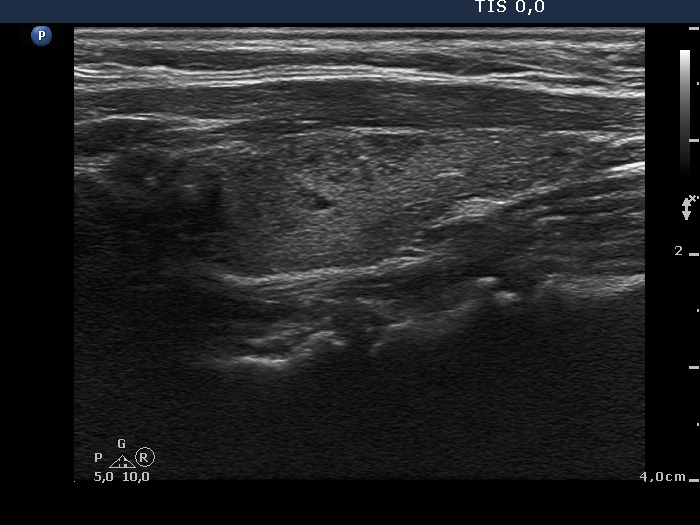

Consecutively operated patients with autoimmune thyroid disease - case 60 (554) (ultrasonographic picture 6)

Left lobe, longitudinal scan. In this section, the thyroid is almost echonormal and contains numerous hypoechogenic areas.